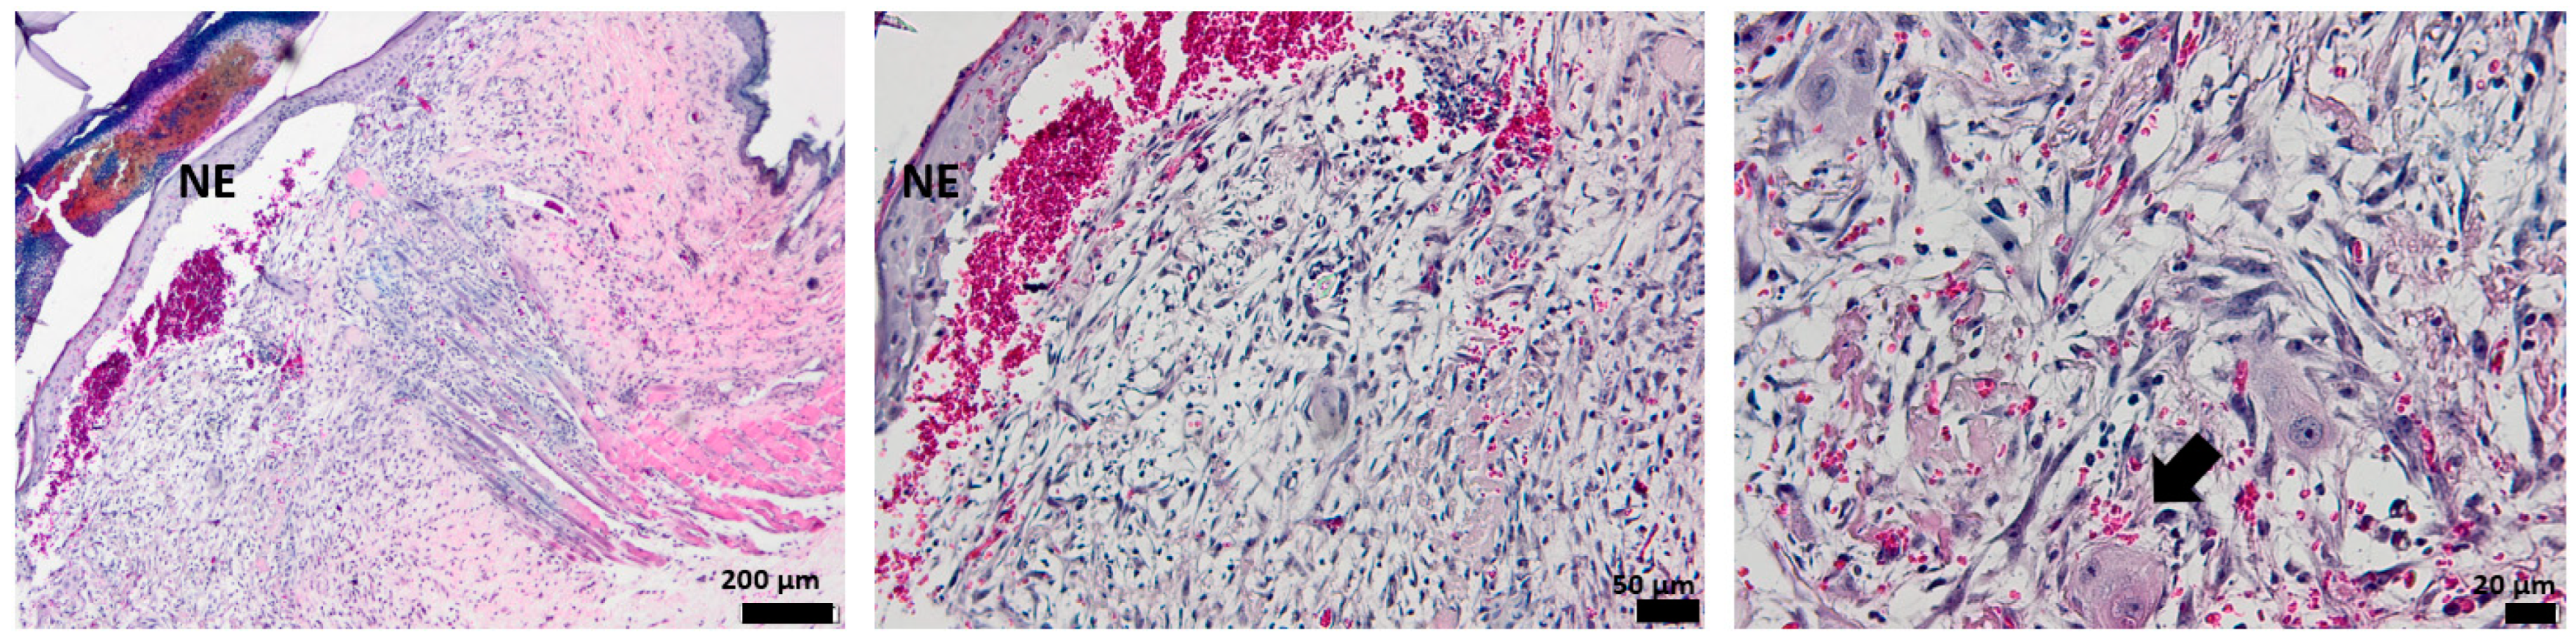

3.5. Histological Aspect of the Keratinization Process (Dane Stain)